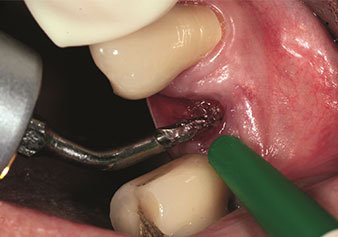

Gestione alveolare

Un’applicazione che viene spesso sottovalutata è l’estrazione atraumatica di radici di denti o frammenti di radici nell’ambito della gestione alveolare. I periotomi sottili, che sono attualmente disponibili in due versioni (EX1 ed EX2 di W&H), possono essere, inoltre, utilizzati per rimuovere con facilità denti che hanno precedentemente subito uno specifico trattamento endodontico o con radici anchilosate. Ne consegue l’estrazione di alveoli in cui i tessuti duro e molle sono entrambi completamente intatti in quanto è generalmente possibile evitare la riflessione.

Ciò pone le basi ottimali per un trattamento con impianto immediato o successivo (Figure 1 e 2 inserite grazie alla gentile concessione del Dott. Torsten Conrad, Bingen a. Rhein).